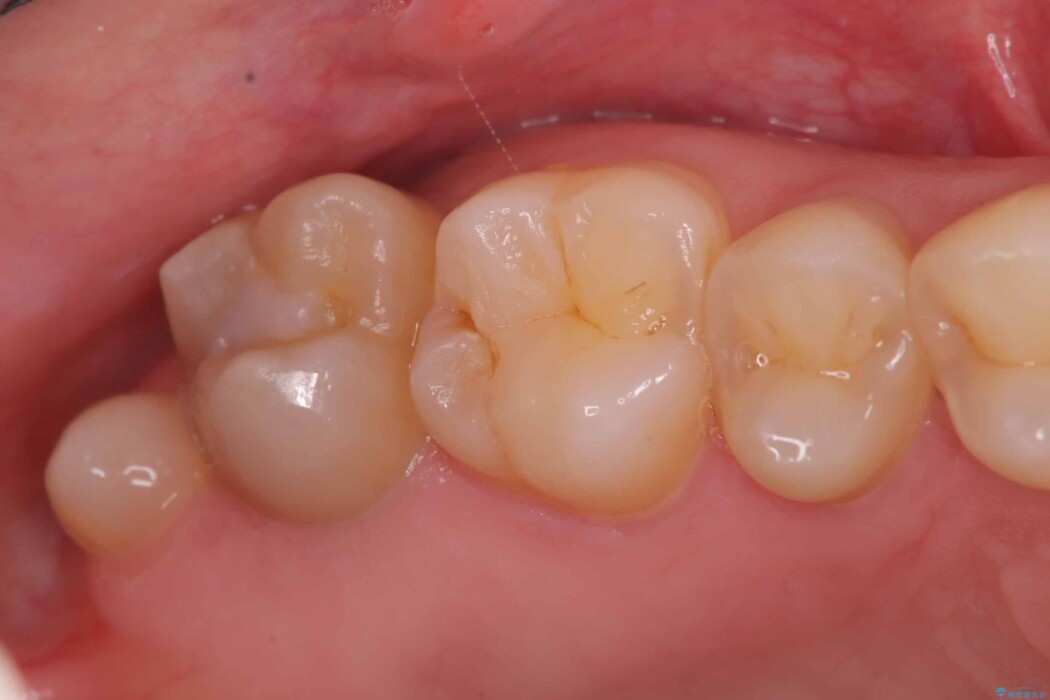

除去後は、再発リスクを抑え長期的な安定を図るために、適合精度が高く劣化しにくいセラミックインレーによる修復を計画しました。